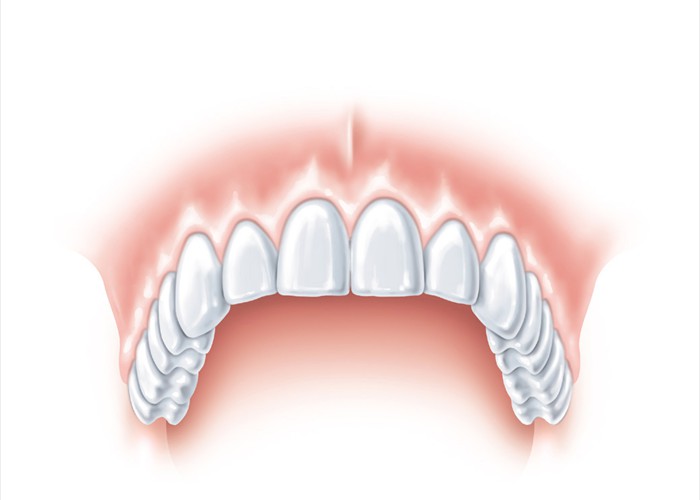

Die fertig eingesetzte Krone ist von den natürlichen Zähnen nicht zu unterscheiden.

Die fertig eingesetzte Krone ist von den natürlichen Zähnen nicht zu unterscheiden.